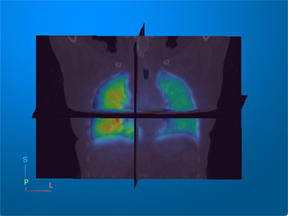

Positron emission tomography (PET) — Visualize metabolic or functional activity in 3-D using radioactive tracers. |

For an example that uses this image [4], see Display Multimodal Medical Image Data from PET and CT. |

[4] Eslick, Enid M., John Kipritidis, Denis Gradinscak, Mark J. Stevens, Dale L. Bailey, Benjamin Harris, Jeremy T. Booth, and Paul J. Keall. “CT Ventilation as a Functional Imaging Modality for Lung Cancer Radiotherapy (CT-vs-PET-Ventilation-Imaging).” The Cancer Imaging Archive, 2022. https://doi.org/10.7937/3PPX-7S22.